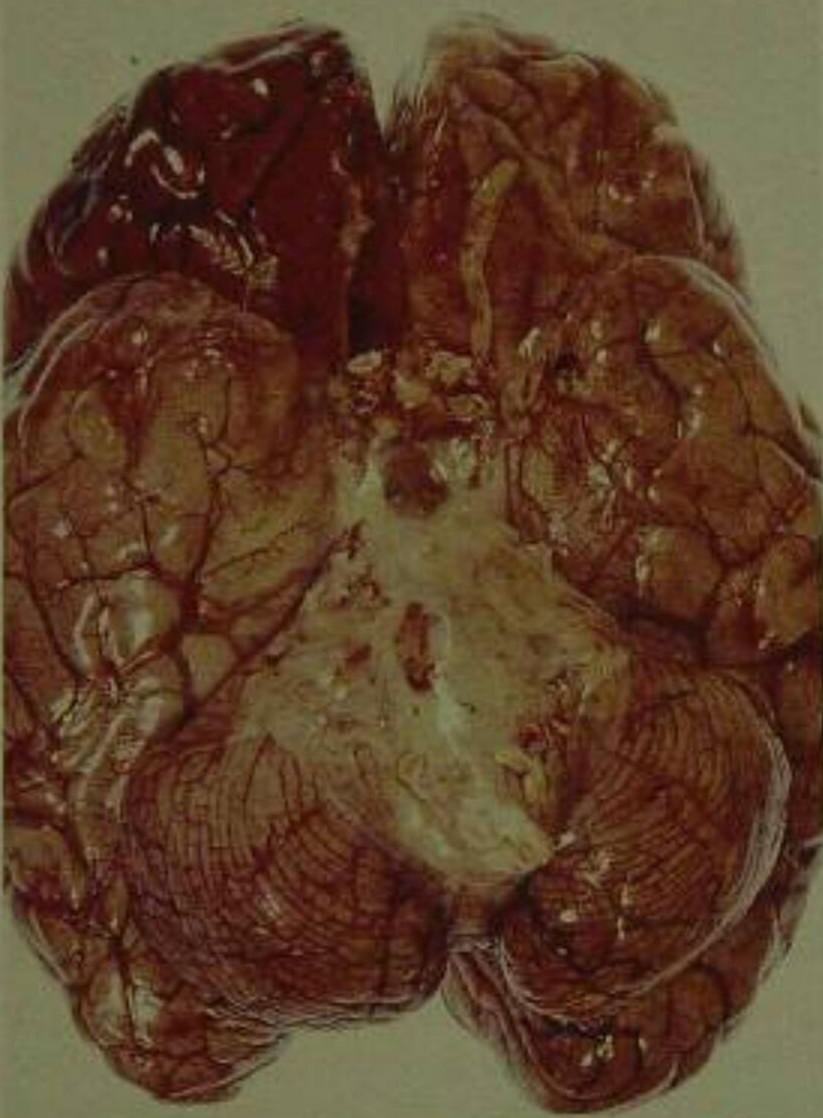

腦膜炎末期

腦膜炎後遺症的